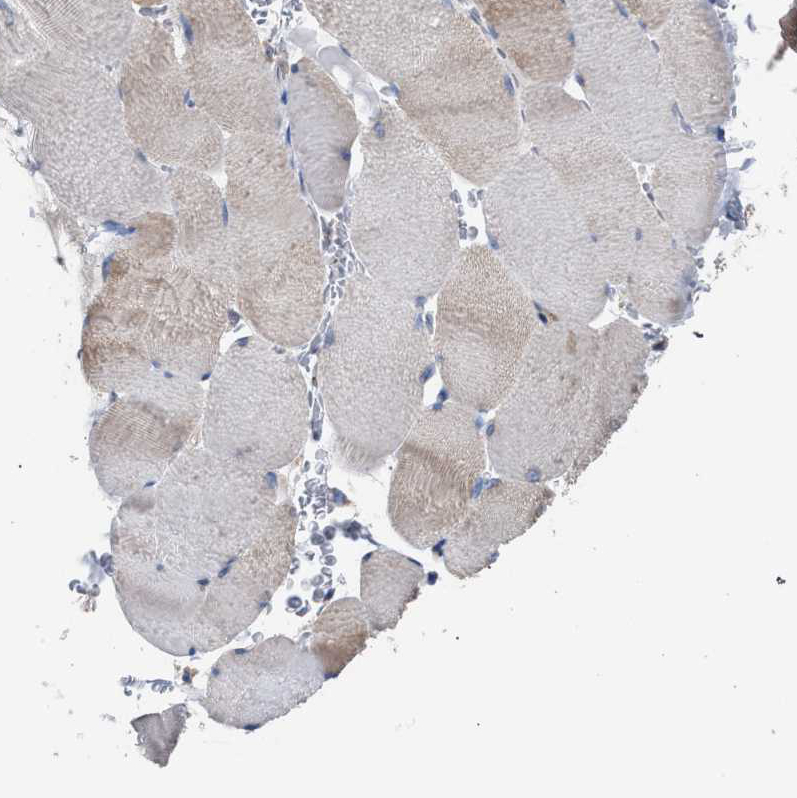

Immunohistochemistry analysis in human duodenum and skeletal muscle tissues using HPA022015 antibody. Corresponding CDR2L RNA-seq data are presented for the same tissues.